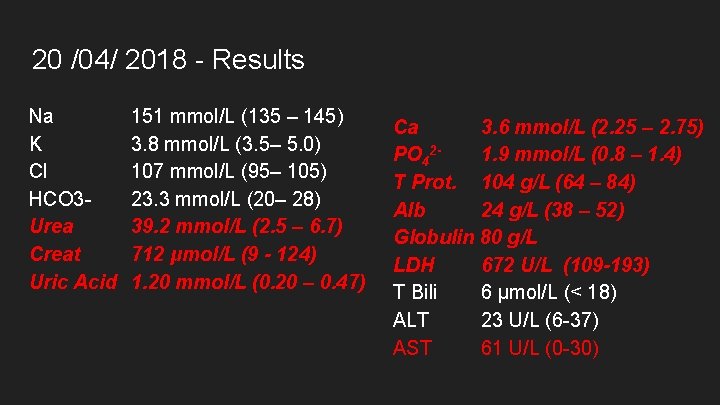

20 /04/ 2018 Na K Cl HCO 3 Urea Creat Uric Acid 151 mmol/L (135 – 145) 3. 8 mmol/L (3. 5– 5. 0) 107 mmol/L (95– 105) 23. 3 mmol/L (20– 28) 39. 2 mmol/L (2. 5 – 6. 7) 712 μmol/L (9 - 124) 1. 20 mmol/L (0. 20 – 0. 47) Ca 3. 6 mmol/L (2. 25 – 2. 75) PO 421. 9 mmol/L (0. 8 – 1. 4) T Prot. 104 g/L (64 – 84) Alb 24 g/L (38 – 52) Globulin 80 g/L LDH 672 U/L (109 -193) T Bili 6 μmol/L (< 18) ALT 23 U/L (6 -37) AST 61 U/L (0 -30)

20 /04/ 2018 - Results Na K Cl HCO 3 Urea Creat Uric Acid 151 mmol/L (135 – 145) 3. 8 mmol/L (3. 5– 5. 0) 107 mmol/L (95– 105) 23. 3 mmol/L (20– 28) 39. 2 mmol/L (2. 5 – 6. 7) 712 μmol/L (9 - 124) 1. 20 mmol/L (0. 20 – 0. 47) Ca 3. 6 mmol/L (2. 25 – 2. 75) PO 421. 9 mmol/L (0. 8 – 1. 4) T Prot. 104 g/L (64 – 84) Alb 24 g/L (38 – 52) Globulin 80 g/L LDH 672 U/L (109 -193) T Bili 6 μmol/L (< 18) ALT 23 U/L (6 -37) AST 61 U/L (0 -30)